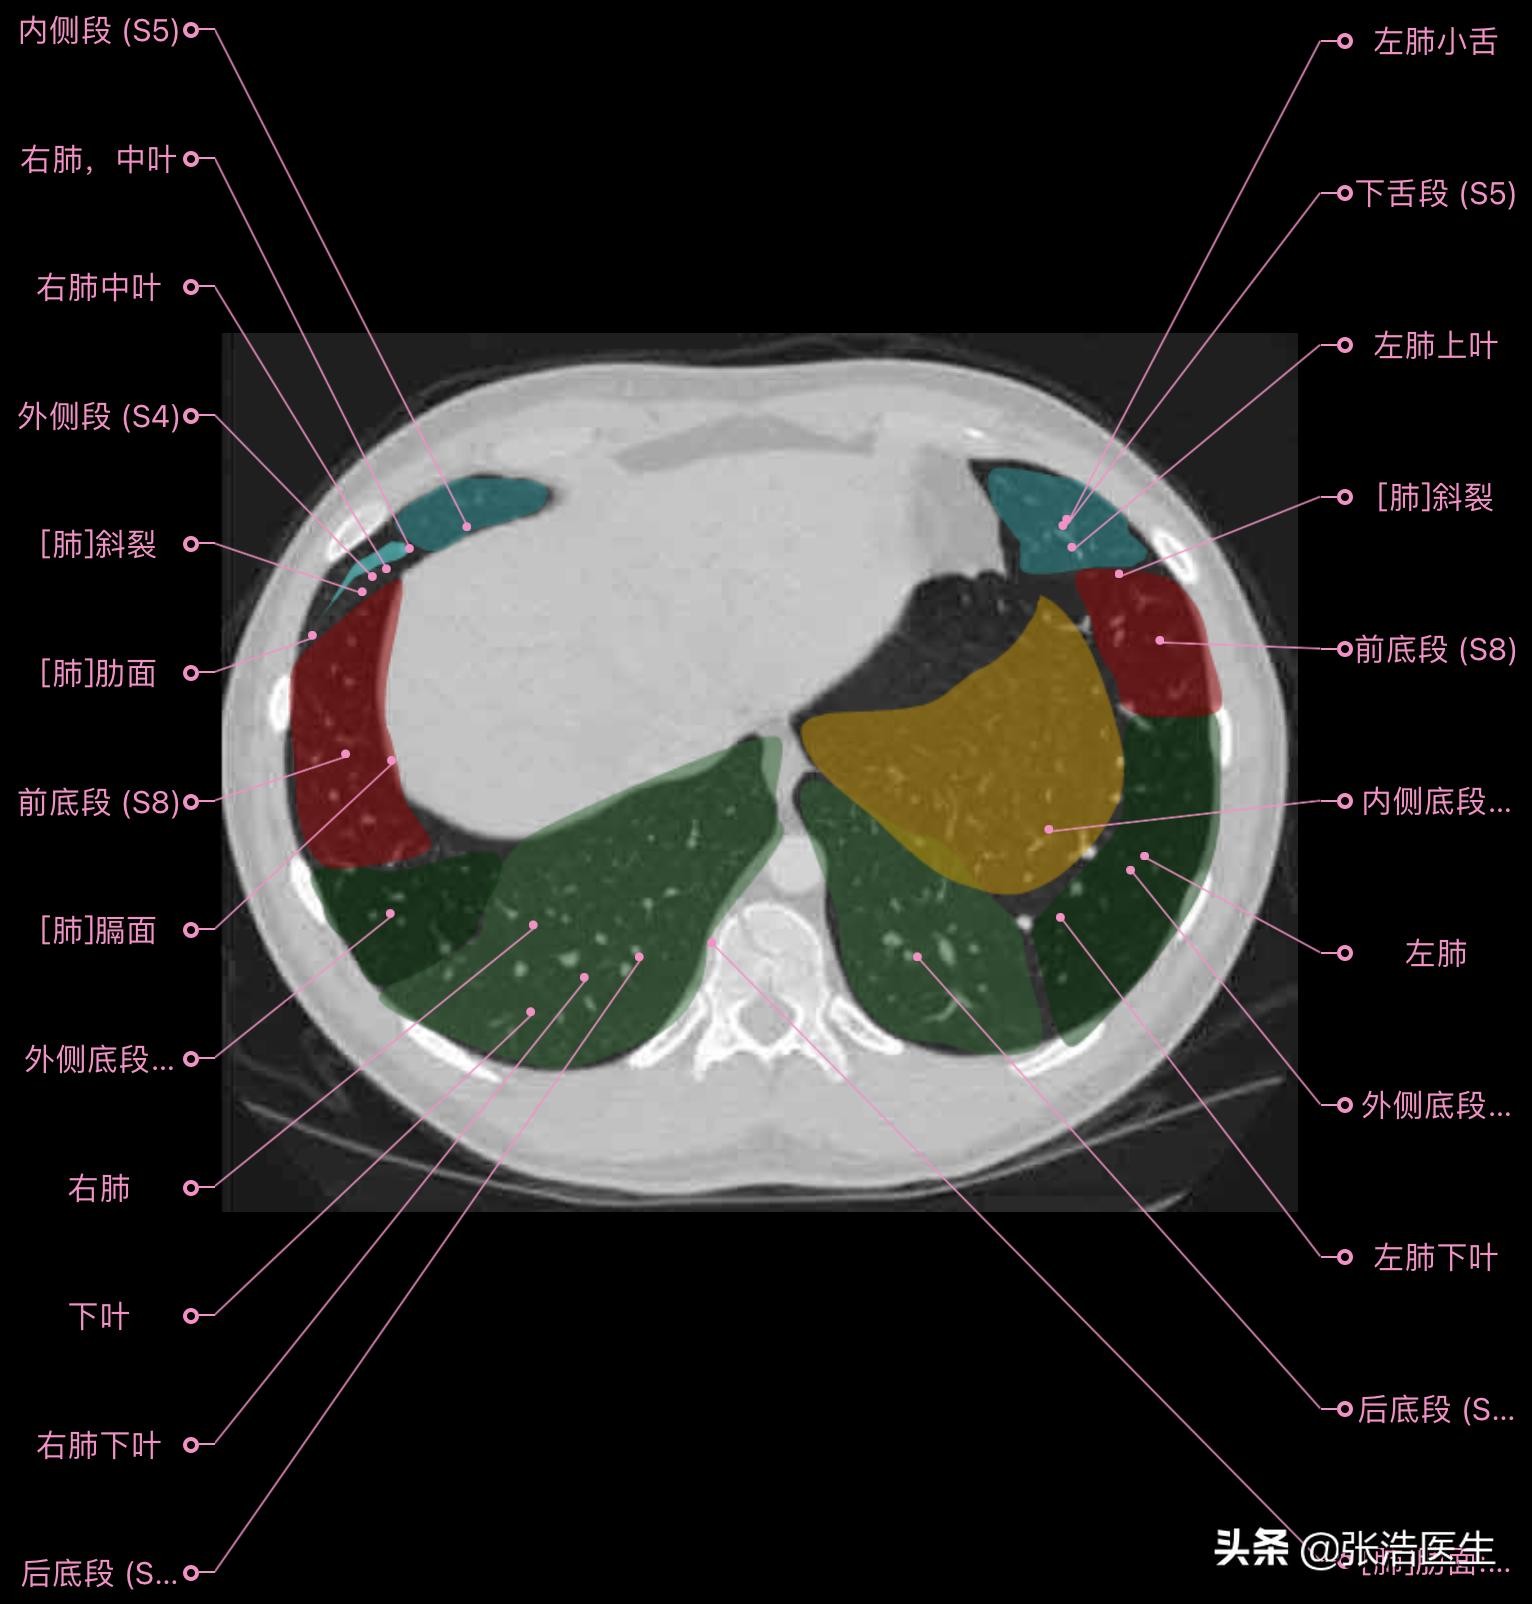

肺部CT横断面 高清解剖图谱

精选15层常用解剖断面

每一层都带有详细标注,值得收藏学习!

肺部CT横断面高清解剖图谱(图层8)